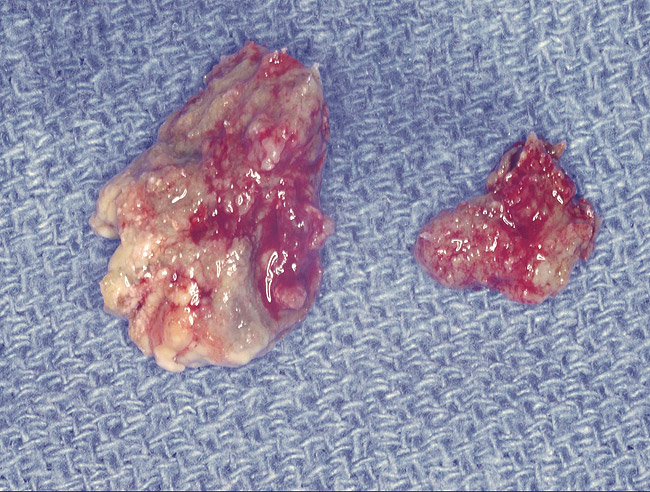

Figure 15  Removal of the necrotic bone material.

Figure 15

Figure 16  Necrotic bone.

Figure 16

As stated earlier, spontaneous osteonecrosis is also possible. Figure 14 shows a case of spontaneous BRONJ resulting from wearing an ill-fitting denture. The patient had noticed the foreign material, but chose not to act on it. When the material was removed in the dental office (Figure 15 and Figure 16), blood streamed from the nose so severely that the patient had to be sent to an ear, nose, and throat (ENT) physician. The ENT took a computed tomography scan, which showed a large radiolucency in the upper left quadrant where the foreign material once had been (Figure 17). A review of the radiograph (Figure 18) showed that bone in the maxillary arch had decreased mineral density compared with the mandible. The biopsy report found necrotic bone with organisms consistent with actinomyces. These findings were consistent with biopsies found in the literature.22 When the patient returned for a 1-week follow-up, she still had signs of infection and the site had a foul odor and a discharge (Figure 19). The patient was informed that she should follow up with the ENT and return to the dental office after the infection had been resolved.